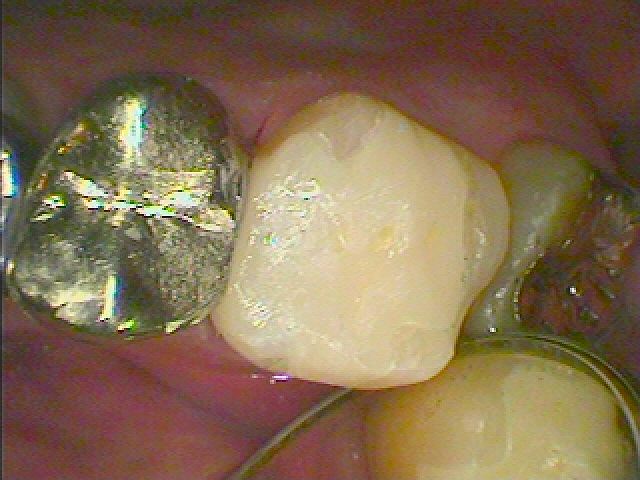

左上の4番部も銀歯を外して白いセラミックへやり変えていきます

虫歯を除去して白い樹脂にて覆罩しています

セレックセラミック(1本2万5千円)にて本来の歯の要旨を取り戻しました

銀歯と比べても綺麗で喜んでいただきました